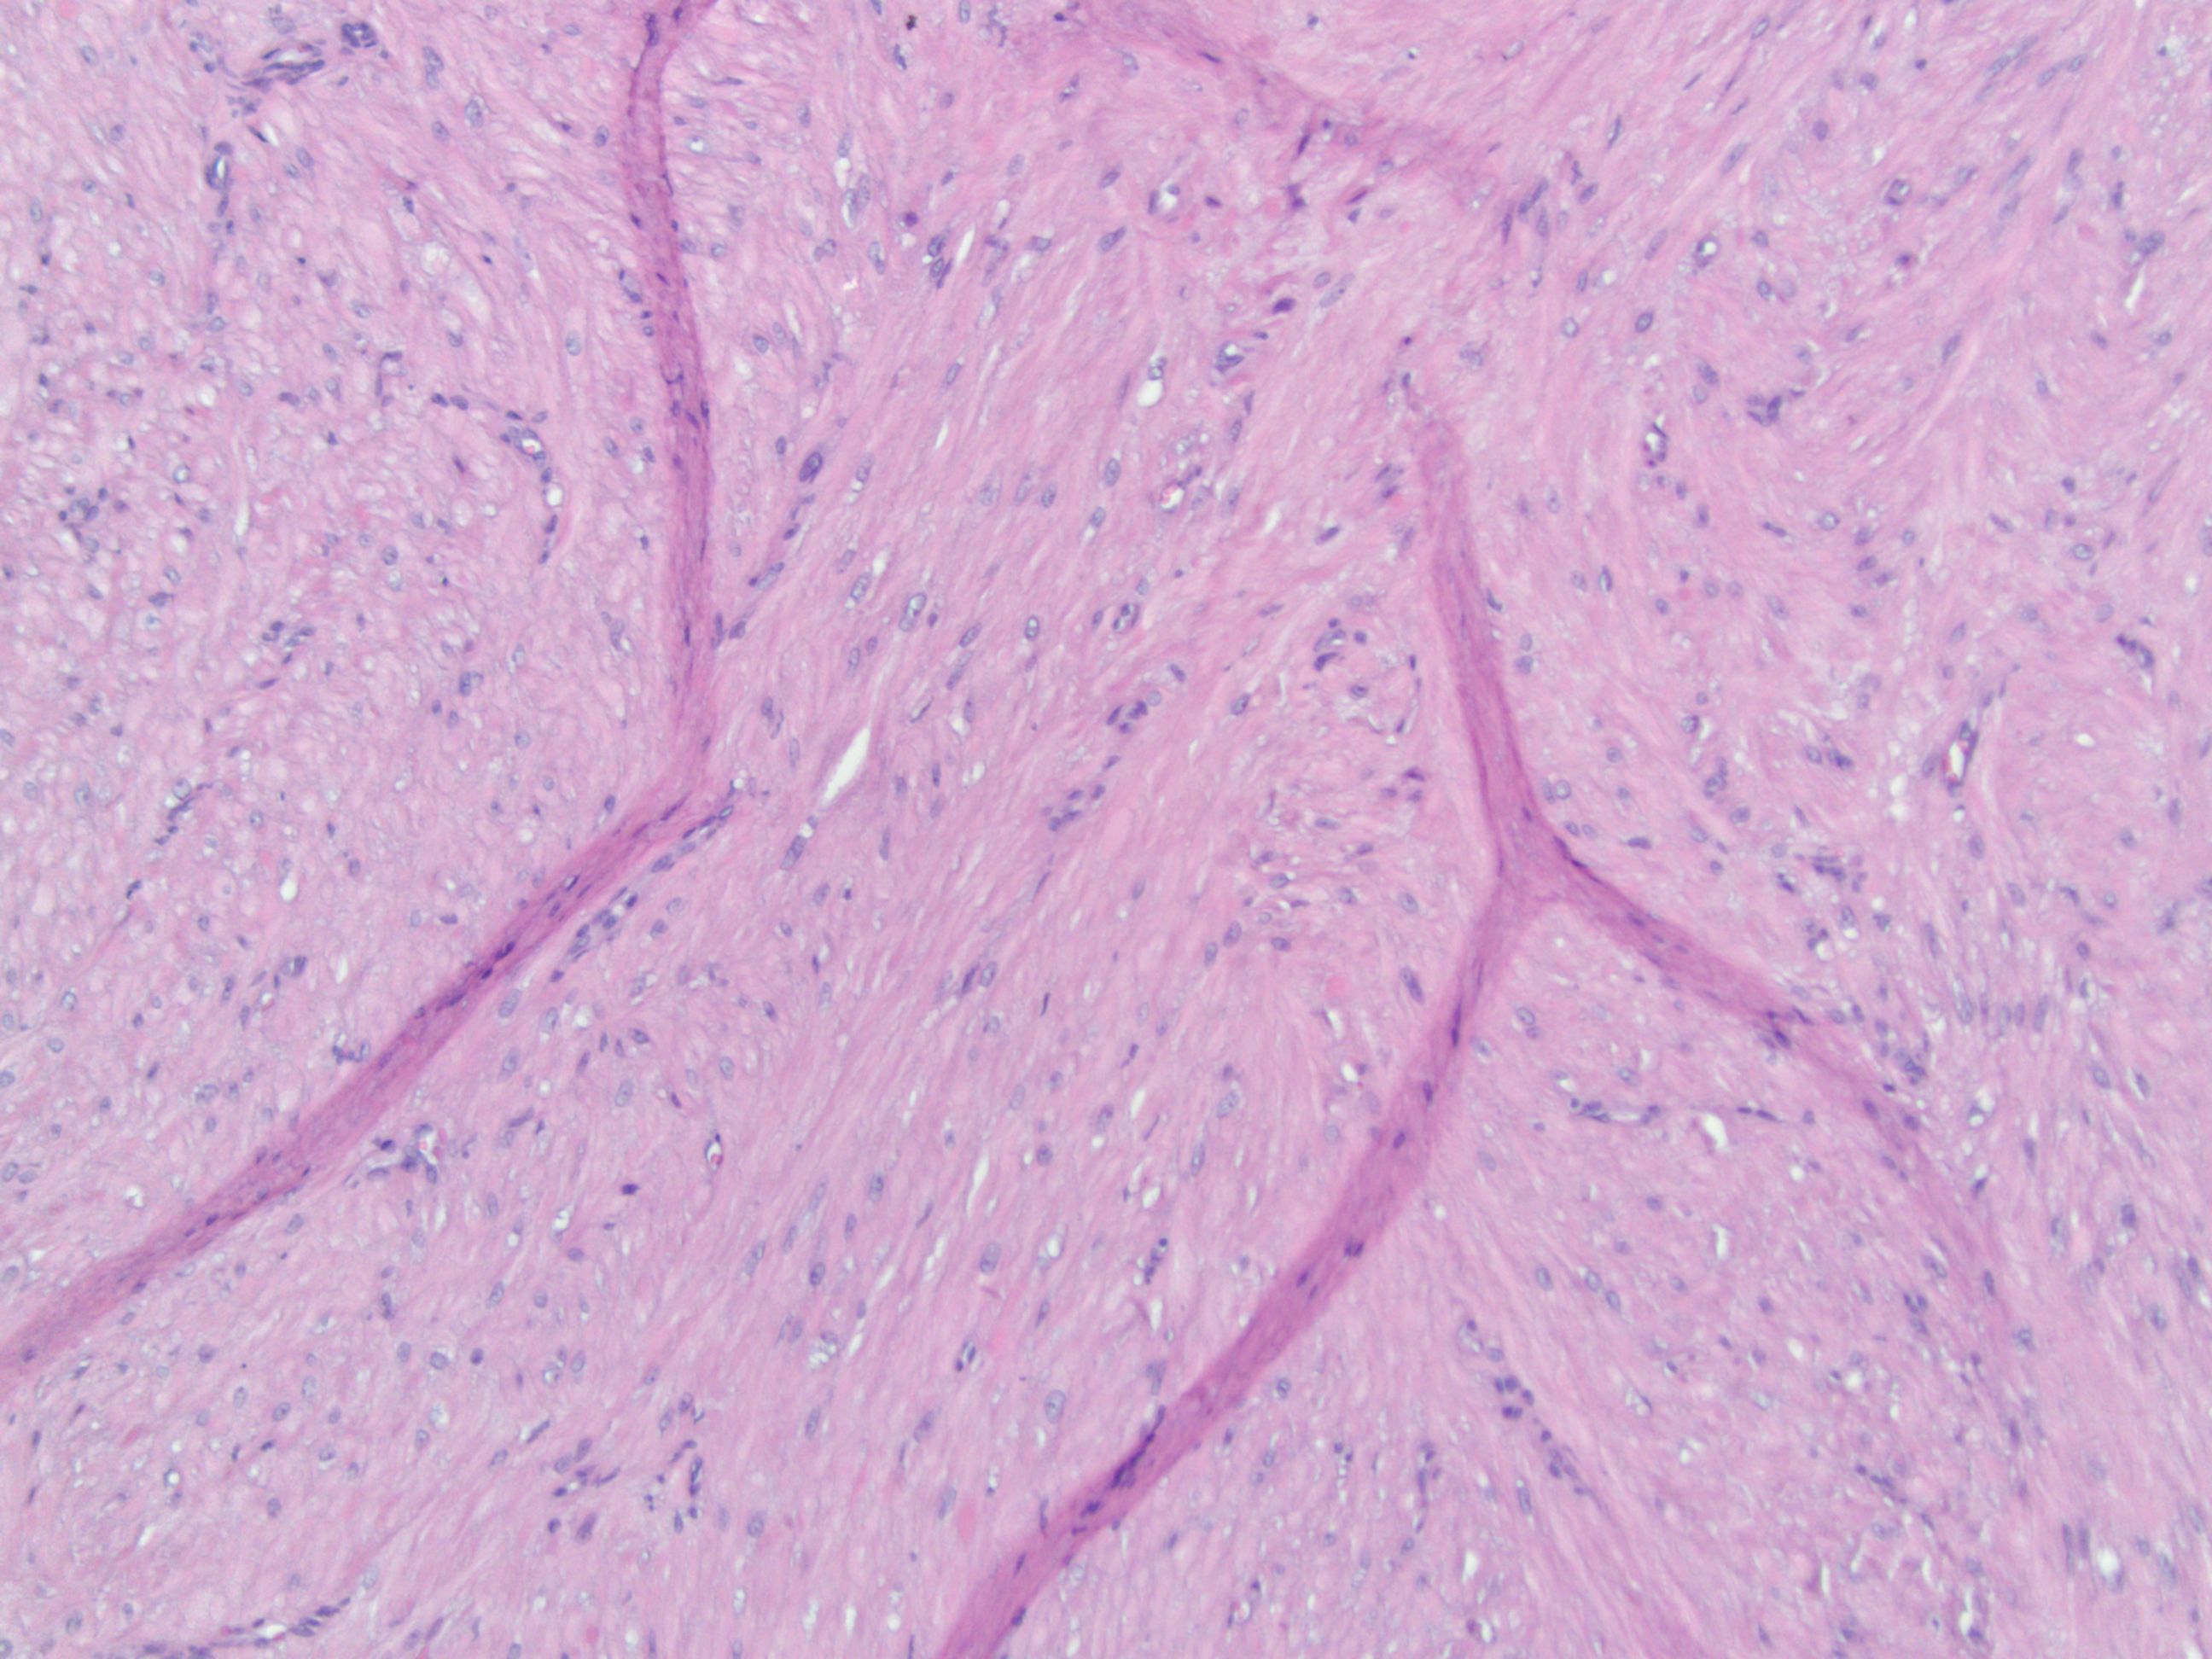

Histologically, angioleiomyomas have a unique pattern with several tiny vascular gaps surrounded by bundles of spindle-shaped smooth muscle cells.